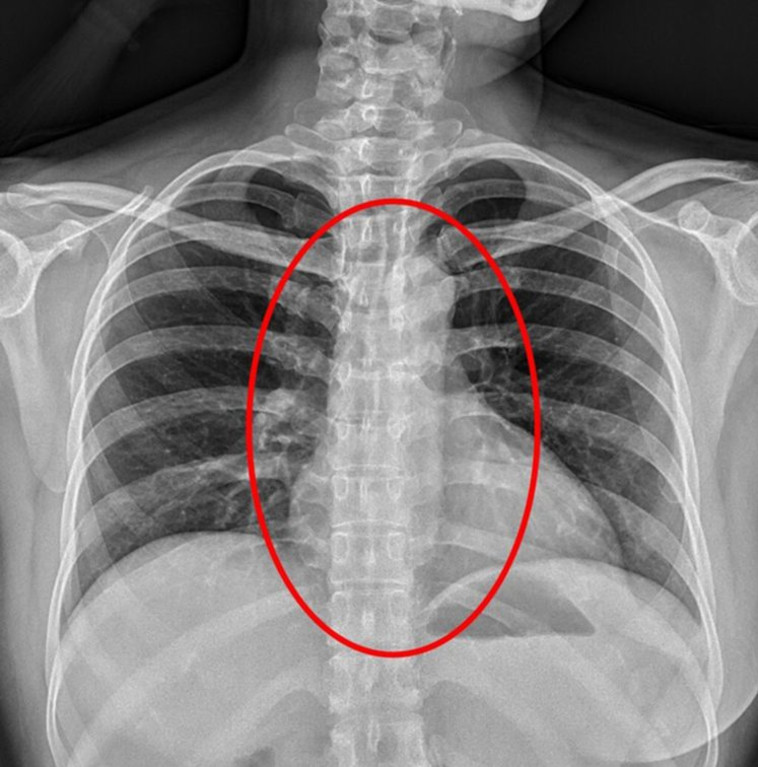

הצל שנמצא בצילומי הרנטגן של היצאנית. צילום מסך

הצל שנמצא בצילומי הרנטגן של היצאנית. צילום מסך | הצל שנמצא בצילומי הרנטגן של היצאנית. צילום מסך

לאחר החקירה, היצאנית המבוהלת נלקחה לבית החולים ג'ן-איי בעיר טאיצ'ונג, שם התגלה "צל" בבית החזה שלה בצילומי רנטגן, שהחוקרים מאמינים שהוא הקונדום. רופאים בבית החולים טענו שאם האישה אכן בלעה את הקונדום, היא סיכנה עצמה בכך שיתכן שהוא נתקע בדרכי הנשימה שלה, או בתוך מערכת העיכול שלה. אם זה מה שיקרה, אמרו, דאנג תאלץ לעבור ניתוח להוצאתו מגופה. אם זאת, יתכן שהוא יתעכל ללא הפרעה ויצא בדרך הטבעית.